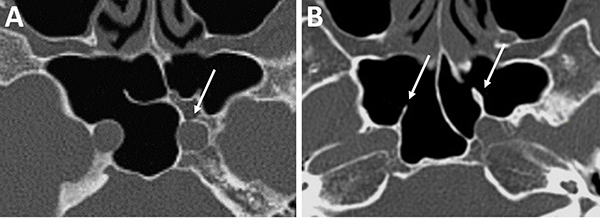

Respecto a los ostium esfenoidales, cabe destacar que son el punto de entrada óptimo al seno esfenoidal. En caso de ser dificultosa su localización (situación frecuente) se podría ingresar al seno esfenoidal aproximadamente 1,5 cm por encima del borde superior de la coana (fig. 11).23,13

El grado neumatización del seno esfenoidal se puede clasificar en selar, pre selar y conchal (fig. 12).1,29,30,58 En el tipo conchal, el área bajo la silla turca es de hueso sólido sin neumatización. En el tipo preselar, el área neumatizada no penetra más allá del plano perpendicular de la pared selar. En el tipo selar, presente en el 86% de los individuos, la región neumatizada se extiende al cuerpo del esfenoides bajo la silla turca, pudiendo extenderse hacia posterior. Esta característica del seno es importante ya que ante la presencia de un tipo conchal es recomendable la utilización de neuronavegación.23,58

Al observar el seno esfenoidal debemos tener en cuenta la presencia de tabiques internos. Estos no deben ser tomados como referencia de línea media por su variabilidad. En este sentido, un dato cardinal es que un 90% los mismos se dirigen a las carótidas (fig. 13).1,15,23

La distancia intercarotidea determina el campo quirúrgico; a menor distancia es menor el campo y mayor el riesgo de lesión iatrogénica vascular. Otro punto a tener en cuenta es la presencia o no de cobertura ósea de la misma. En algunas oportunidades se va a encontrar recubierta por una lámina de hueso y, en otras, desprovista de la misma (fig. 13).15,23

Figura 11: Ostium esfenoidales identificables en TC. A) TC corte axial; B) TC corte sagital.

Figura 12: Neumatización del seno esfenoidal en TC cortes sagitales. A) Tipo selar; B) Tipo preselar; C) Tipo conchal.

Figura 13: Relación carótida – septaciones esfenoidales en TC cortes axiales. A) Septum interesfenoidal se inserta sobre meso carotídeo izquierdo (flecha blanca); B) Septaciones incompletas que se insertan sobre meso carotídeo en ambos senos esfenoidales (flechas blancas).

Figura 14: Localización de nervio óptico en TC cortes coronales. A) Nervio óptico dehiscente; B) Nervio óptico en su meso, con variante hiperneumatizada esfenoidal.